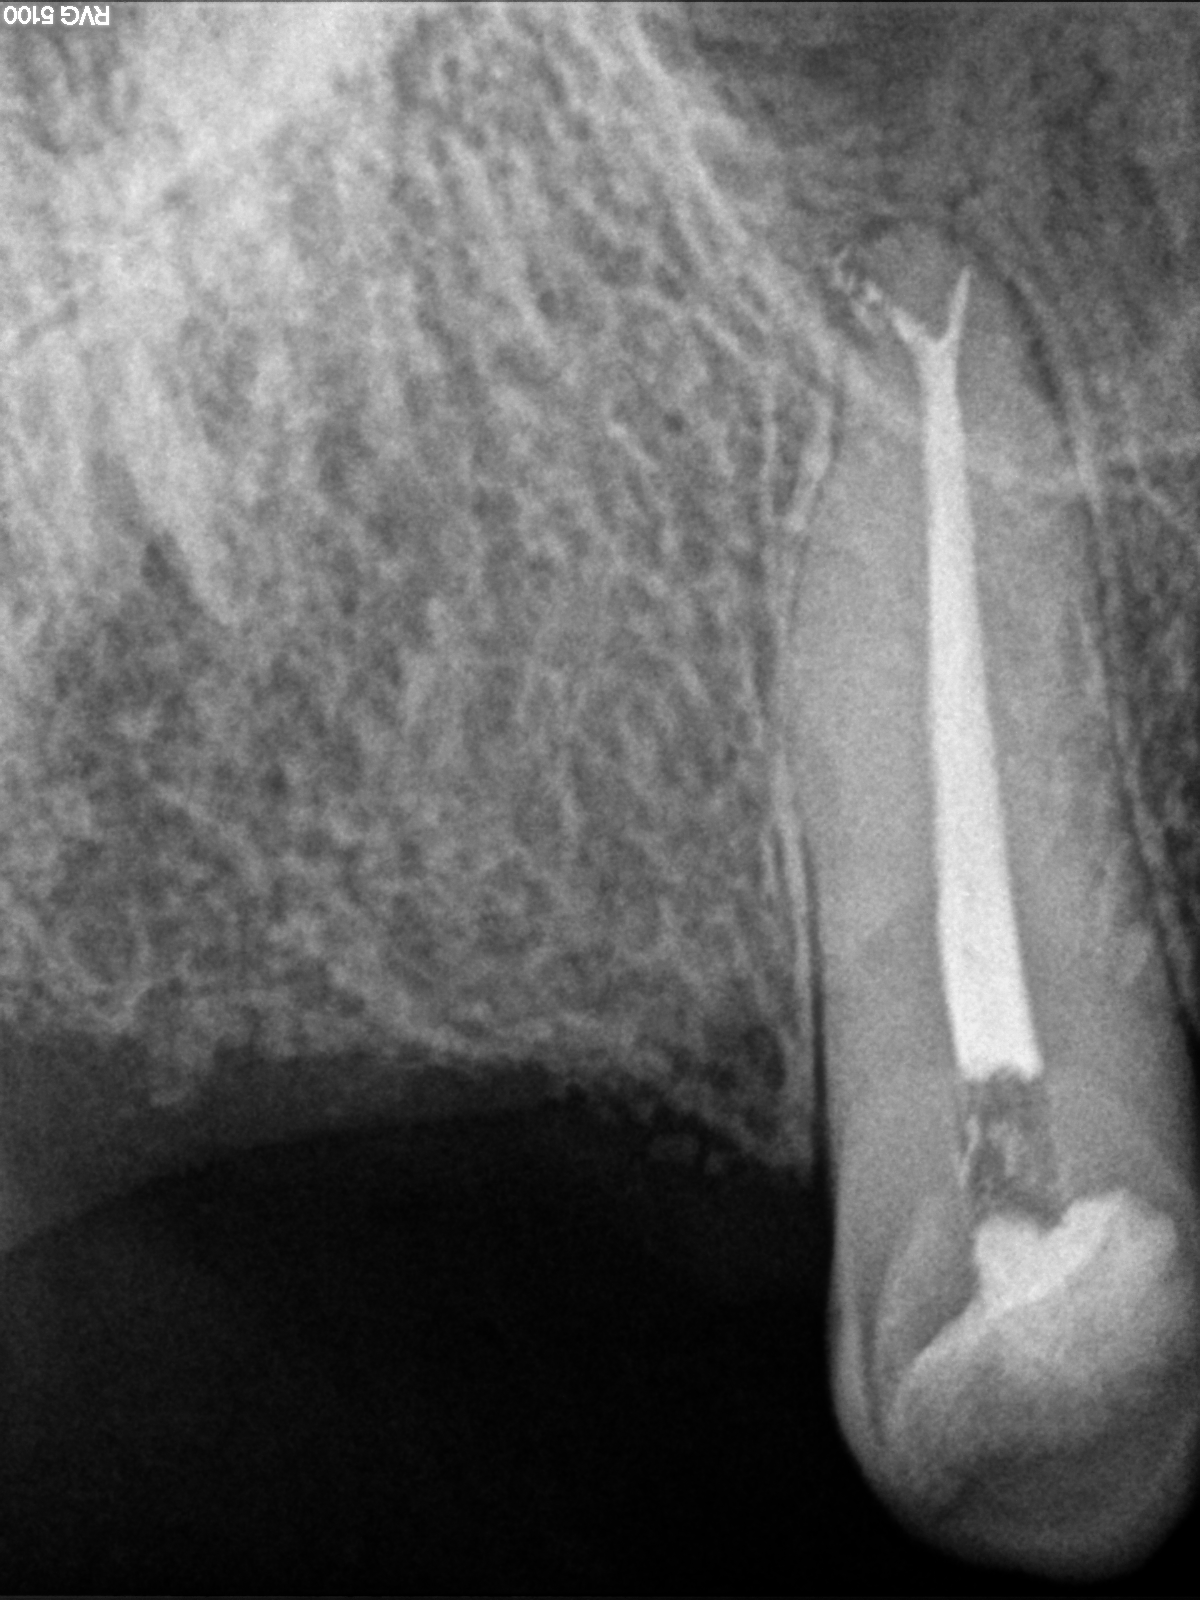

Endodoncia Finalizada Canino Superior